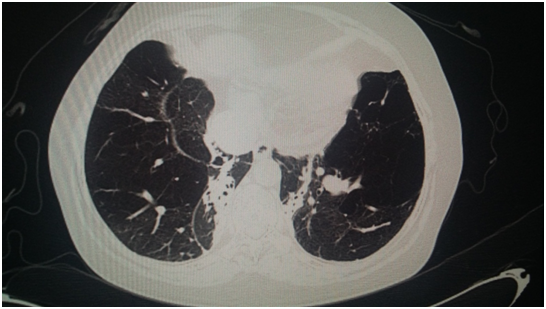

Female of 59 years old, exposed to biomass smoke (index=100 hrs/year), followed as Chronic Obstructive Lung Disease during 9 years; her main symptom has been dyspnea, vital signs HR 86 per min, RR 20 per min, 110/78 mmHg, body temperature 36.6°C, very severe obstruction in spirometry, low Diffusion Capacity, increased Residual Volume, Pulmonary Arterial hypertension by echocardiography (47 mmHg) and arterial gases pH 7.38, PaCO2= 47 mmHg, PaO2 66 mmHg, HCO3 =21.6 and O2 saturation 92.5% with oxygen supply. Radiographic studies Figure 1 showed, bullous emphysema at left lung in conventional chest radiography; and, neurofibromatosis lesions in both hands (Figure 2) and feet (Figure 3) and Computed tomography revealing bilateral emphysema and bullae (Figure 4).

Figure 1 Chest X ray.